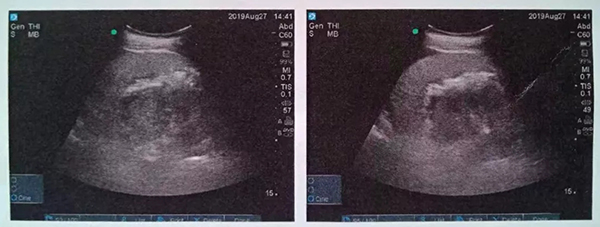

術(shù)中,泌尿外科郭駿博士精心設(shè)計手術(shù)通道,只在患者體表鉆出兩個0.5厘米的小洞,由于患者右側(cè)上位腎位置高,靠近肝臟和肺下葉,容易出現(xiàn)肝臟和肺的損傷,在B超的引導(dǎo)下精確穿刺腎結(jié)石的最高點,逐級擴張后建立皮腎通道。這時屢次“惹禍”的腎結(jié)石清楚的顯露在手術(shù)屏幕上,結(jié)石呈淺黃色,表面覆蓋淺褐色的膿苔,然后使用鈥激光將結(jié)石擊碎后取出。歷時一個半小時,結(jié)石全部清除,手術(shù)結(jié)束。

術(shù)后CT,箭頭所指為腎結(jié)石被徹底清除